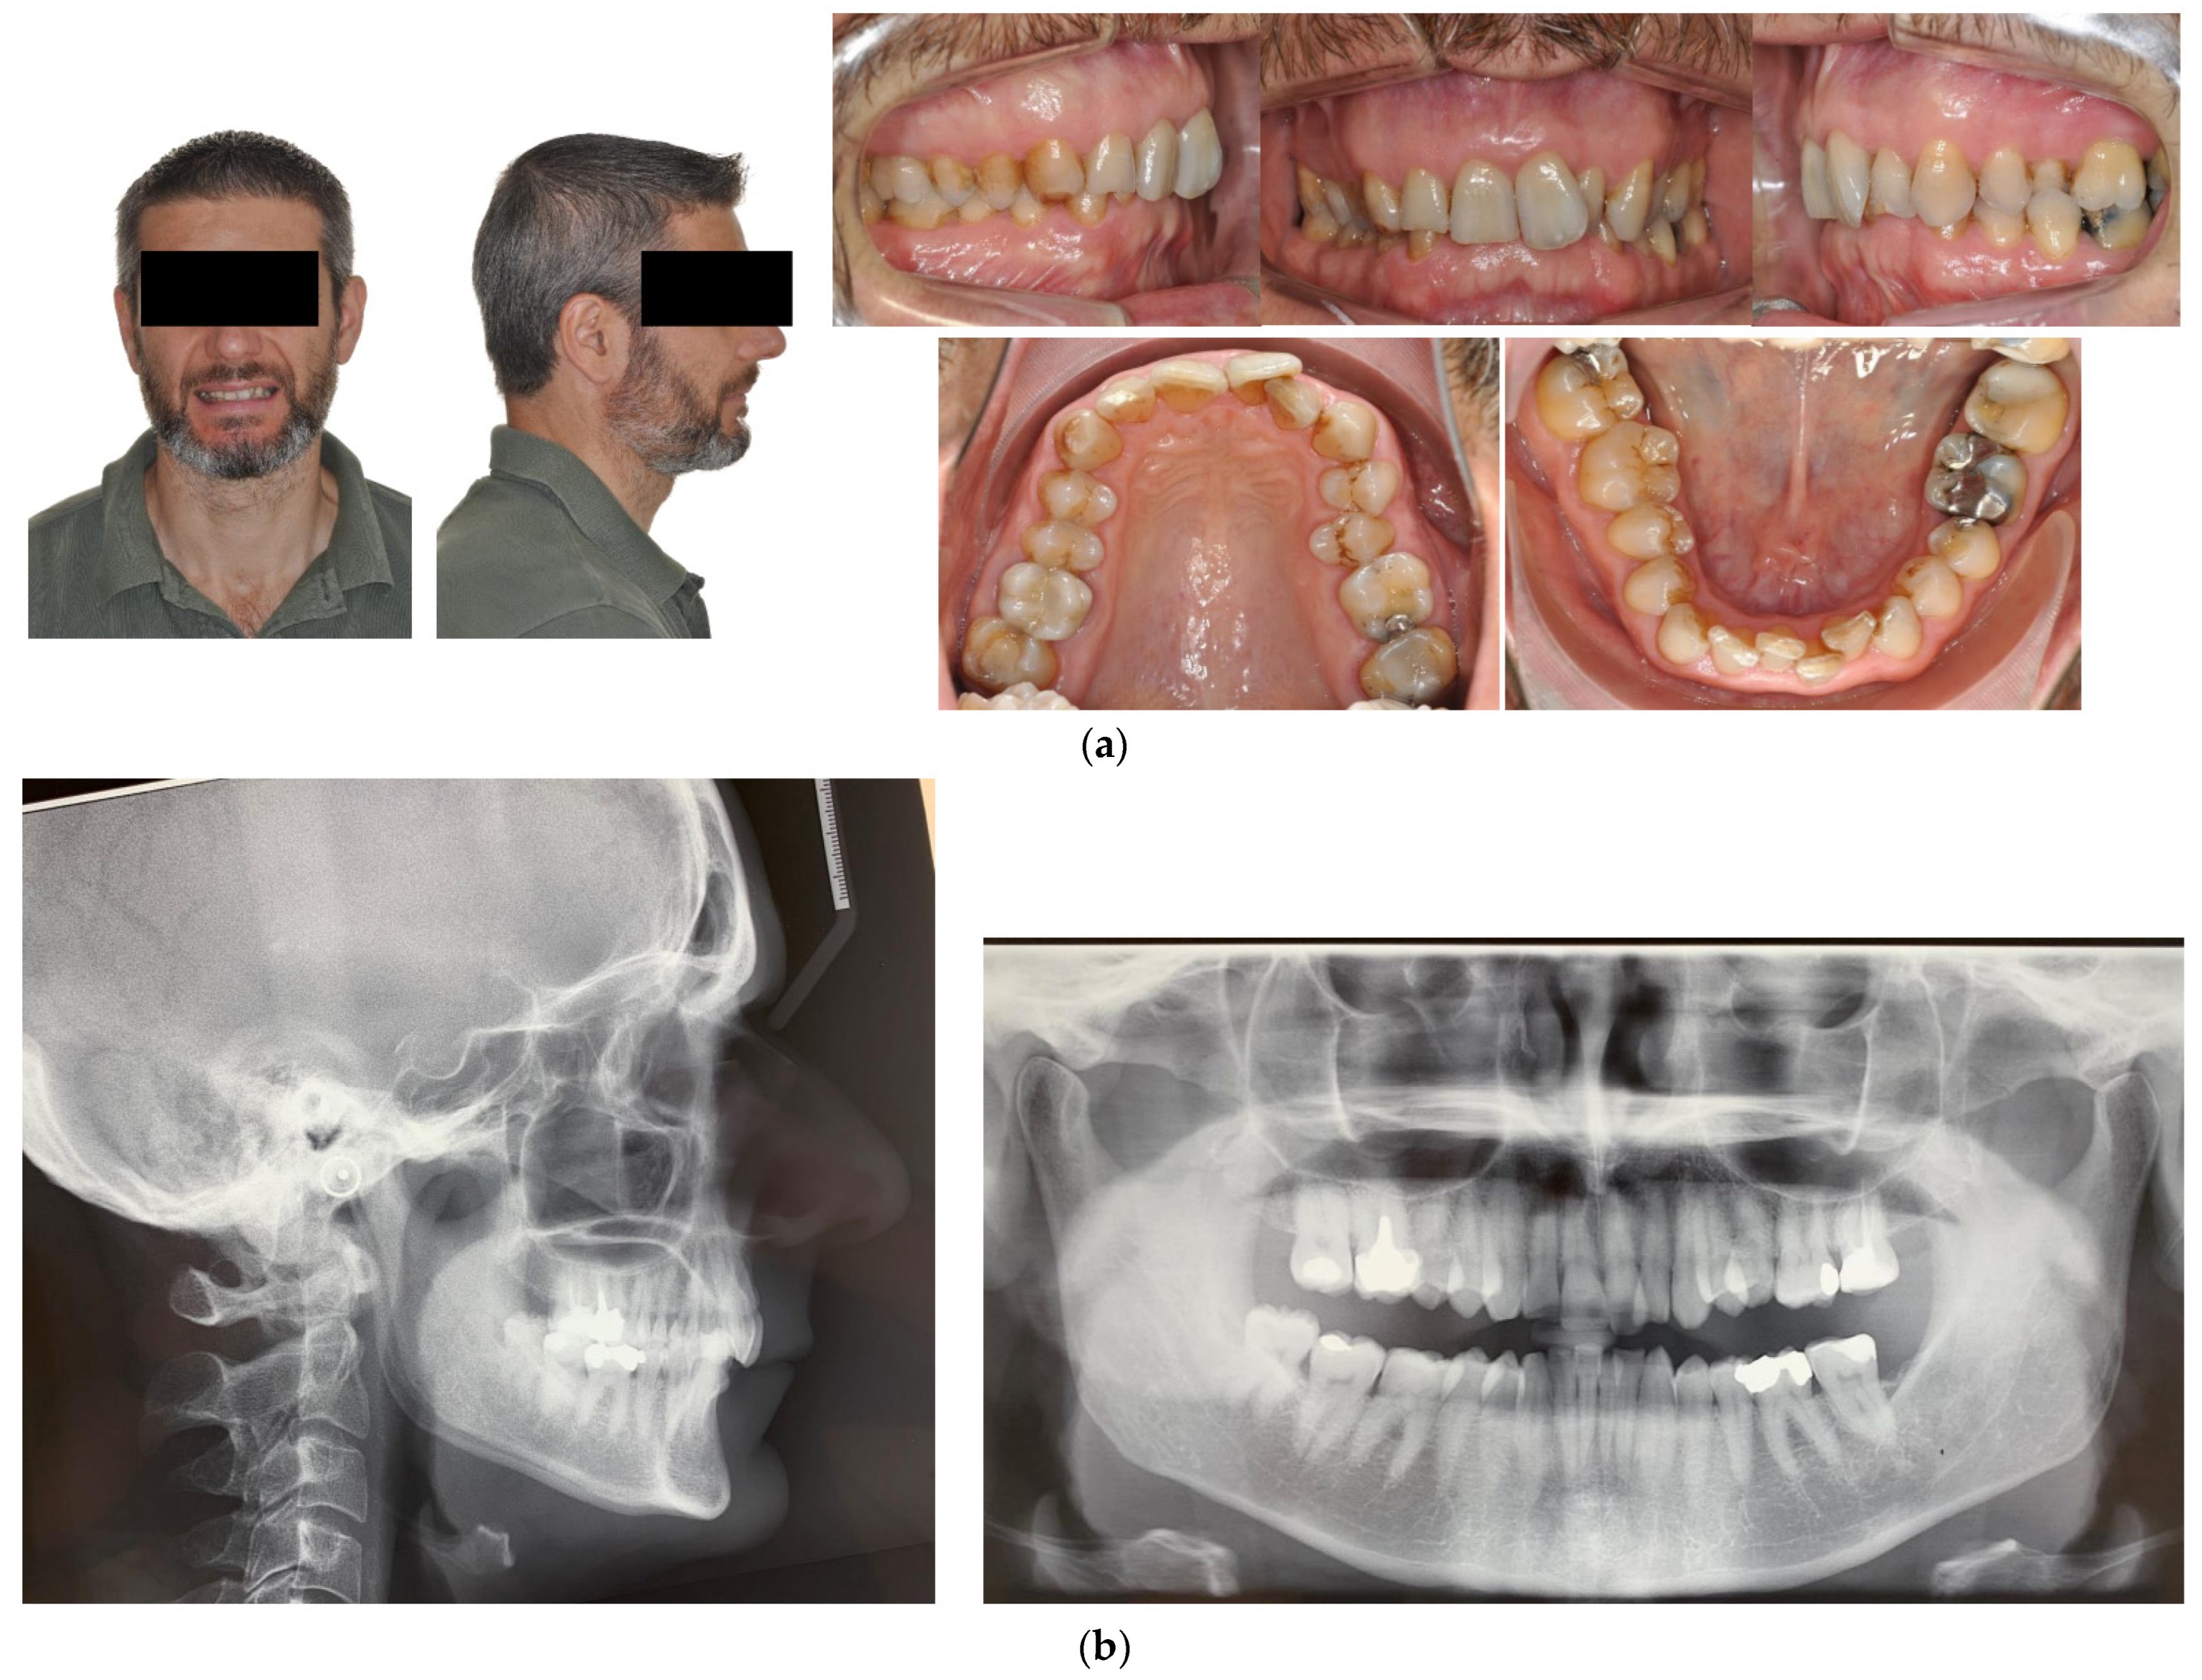

4.1. Case 1: Class II Division 2 with a Deep Bite